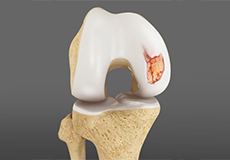

Chondral or Articular Cartilage Defects

The articular or hyaline cartilage is the tissue lining the surface of the two bones in the knee joint. Cartilage helps the bones move smoothly against each other and can withstand the weight of your body during activities such as running and jumping. Articular cartilage does not have a direct blood supply to it, so has less capacity to repair itself.

Osteochondral Defect of the Knee

An osteochondral defect, also commonly known as osteochondritis dissecans, of the knee refers to a damage or injury to the smooth articular cartilage surrounding the knee joint and the bone underneath the cartilage. The degree of damage may range from a rupture of the cartilage to a slight crack of the bone to a piece of the bone breaking off within the joint.

Articular Cartilage Injury

Patients with articular cartilage damage experience symptoms such as joint pain, swelling, stiffness, and a decrease in range of motion of the knee. Damaged cartilage needs to be replaced with healthy cartilage and the procedure is known as cartilage replacement.